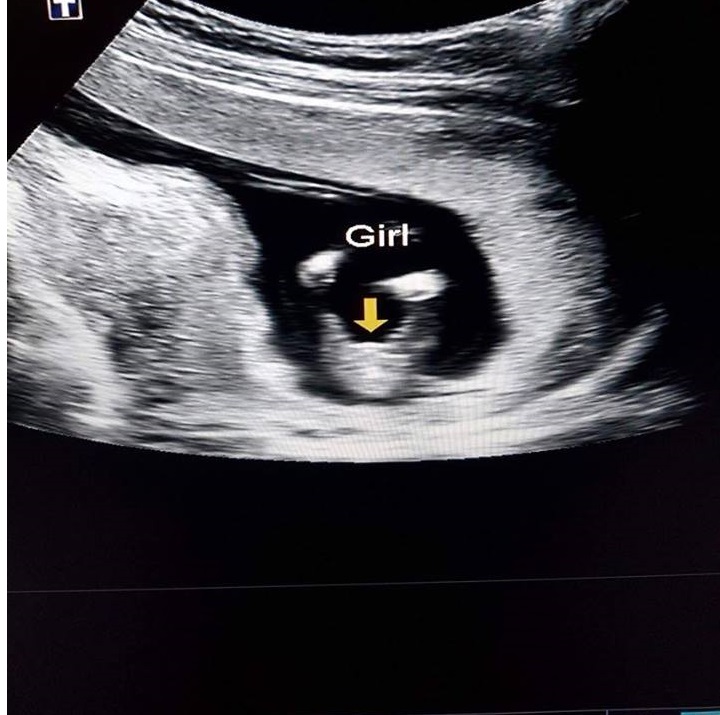

Attachment 35360 *update* confirmed girl at 14 weeks[/SIZE][/SIZE]

Wow, I guess that was a leg, LOL. Congrats on your girl!